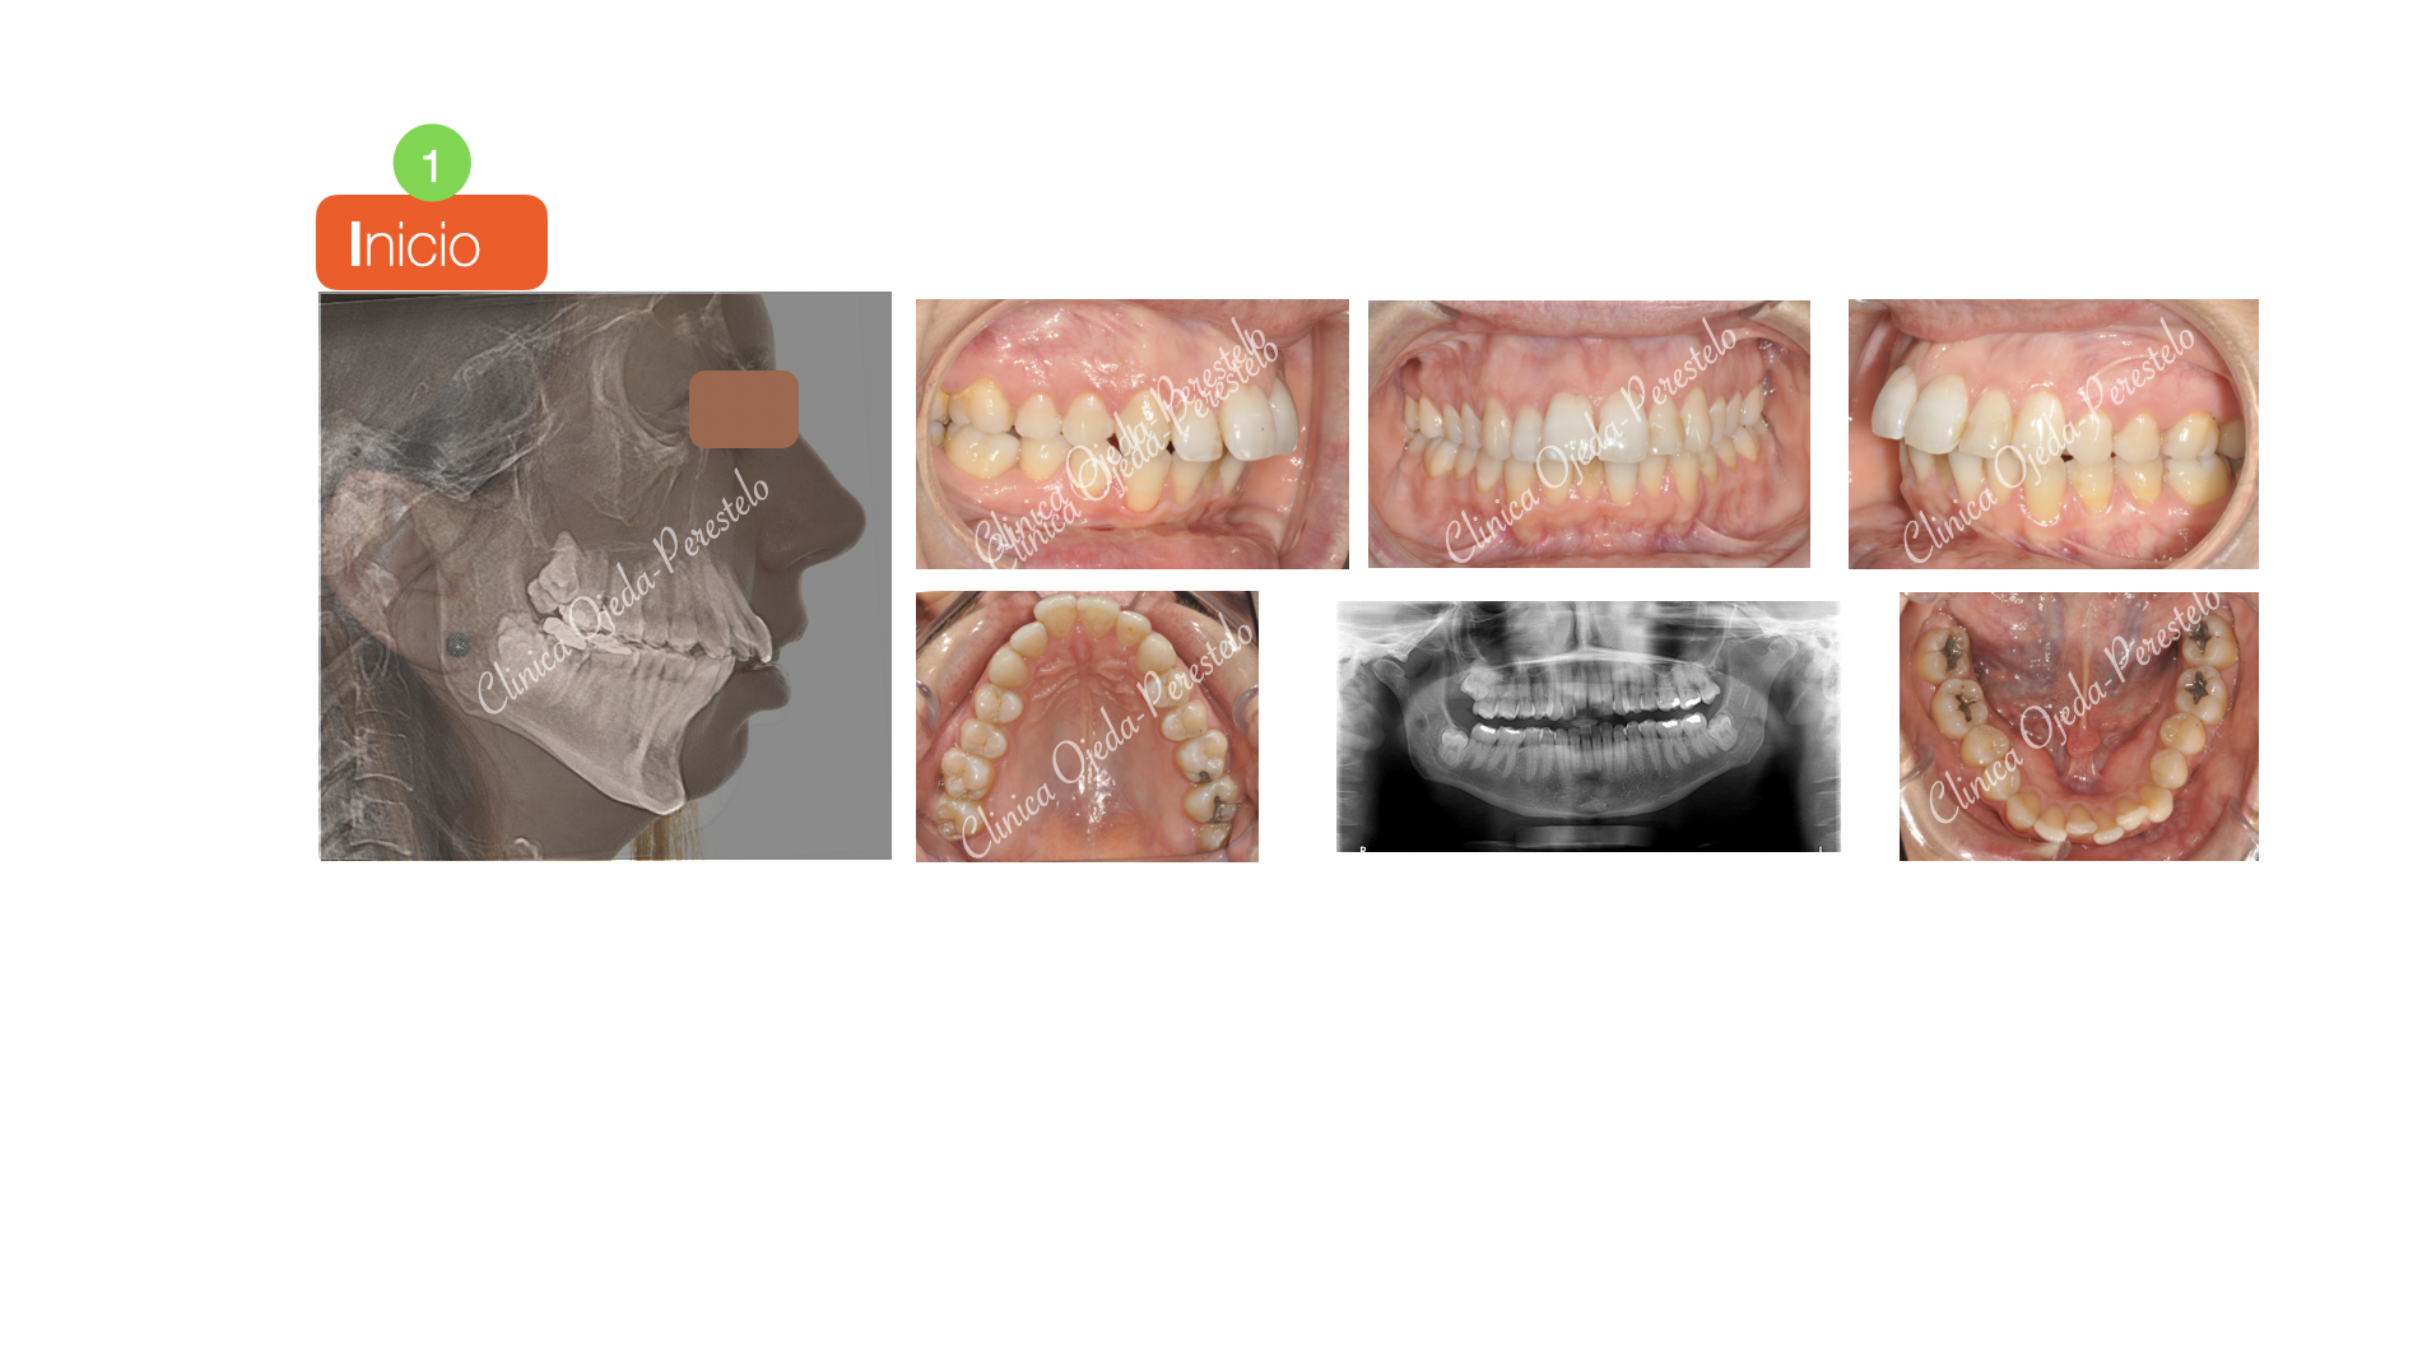

Clase II severa en Mandíbula Hipoplásica

Paciente que consulta porque tiene dificultad para respirar por la nariz y mantener la boca cerrada.

Decidimos realizar un tratamiento de Cirugía Ortognática Bimaxilar con Biavance y Ortodoncia.

La intervención quirúrgica ha sido realizada por el equipo del Dr Hdez-Alfaro.

La planificación Ortodóncia asociada a la Cirugía que debía llevar la paciente se realizó con brackets y extraciones (Sistema Damon).